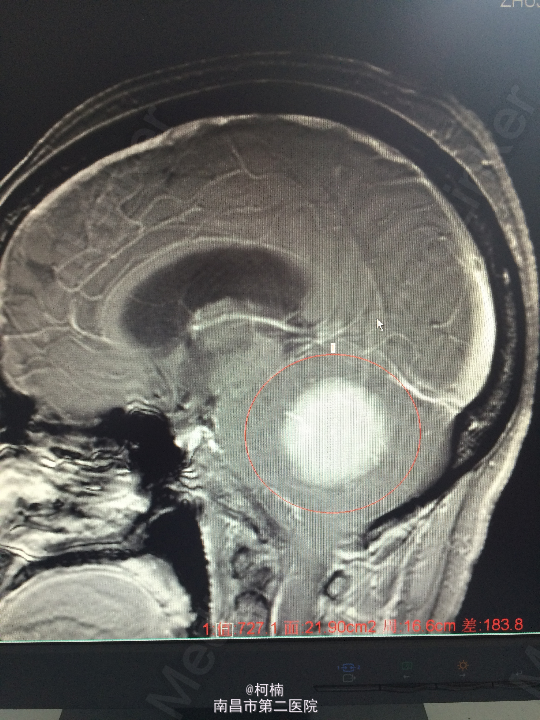

主诉:反复头晕、头痛伴呕吐及行走不稳10月余 病史:患者老年女性,55岁,10余月前开始出现头晕、头痛伴呕吐及行走不稳,无肢体乏力、肢体抽搐、意识障碍等不适,于当地医院诊治行头颅MR提示:右侧小脑角占位,考虑肿瘤。 查体:神经系统体查未见明显异常

查体:神经系统体查未见明显异常 辅助检查:头颅MR提示右侧桥小脑区占位性病变,考虑脑膜瘤。四脑室狭窄,变形,幕上脑室积水,小脑扁桃体疝

诊断:右侧小脑脑膜瘤 处理:先行介入栓塞肿瘤供血动脉,再行开颅手术治疗,术后予组织病理检查,提示:脑膜瘤